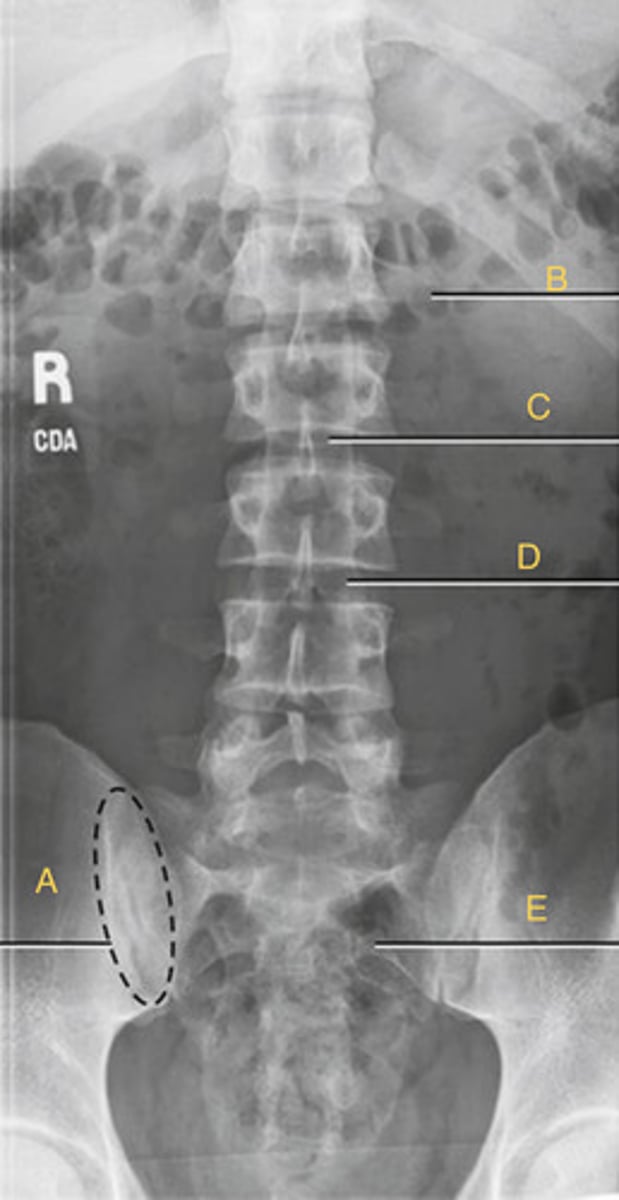

L5 R transverse process

A.

L4 Lower lateral portion

B.

L4 spinous process

C.

L3 R inferior articular process

D.

L4 L superior articular process

E.

L1-2 intervertebral disk space

F.

AP Lumbar

What position?